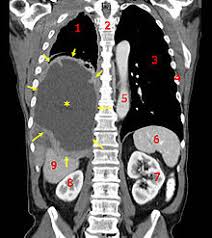

The most basic test is a chest x-ray. The x-ray will show abnormalities involving the lungs, such as irregular thickening of the pleura, lowering of the space between the lungs, abnormal mineral deposits, and fluid build up inside of the lungs. A doctor will either take a CT scan (computed tomography scan) or an MRI (magnetic resonance imaging scan) to try and determine the location, size and mass of a possible cancerous growth. The CT scan uses a rotating x-ray beam to create a series of pictures of the body from many different angles. A computer then combines these pictures to produce cross-sectional images of a part of the body. A doctor may need to inject a dye into a vein in order to highlight details on the CT scan. An MRI uses magnetic fields instead of x-rays to create its images. After the magnetic fields capture the information, a computer generates a detailed cross-sectional image.

A physical exam will provide your doctor with information about signs of mesothelioma and other health problems you may be experiencing. Patients with pleural mesothelioma often have fluid in their chest cavity, which is called pleural effusion. A physical exam can also detect the presence of ascites (fluid in the abdominal cavity) in patients with peritoneal mesothelioma. In patients with pericardial mesothelioma, pericardial effusion (fluid in the pericardium) can also be detected during a physical exam by a doctor.

About 75% of mesothelioma occurrences start in the chest cavity. This is known as pleural mesothelioma. Another 10% to 20% is peritoneal mesothelioma which begins in the abdomen. Pericardial mesothelioma, found in the cavity around the heart, is very rare.

Peritoneal mesothelioma involves the abdominal cavity, infiltrating the liver, spleen or bowels. Due to fluid accumulation in the abdominal cavity (ascites), the abdomen appears enlarged. The patients experience nausea, vomiting, fever and difficulty in moving their bowels.